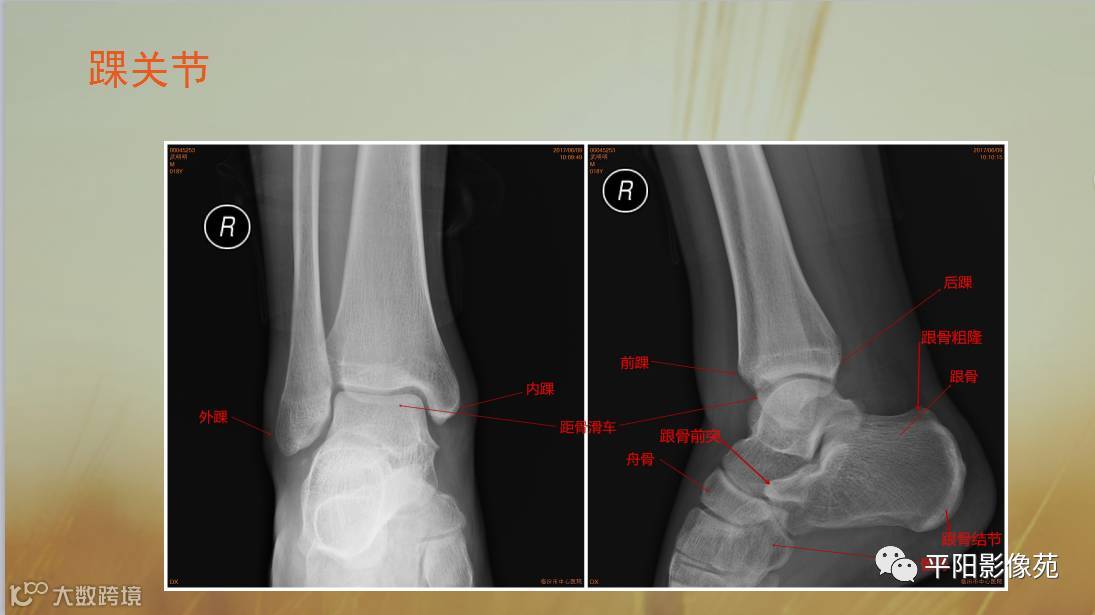

四肢骨骼X线解剖